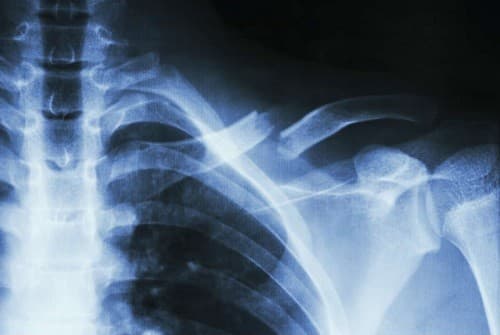

Gãy xương đòn là chấn thương hay gặp nhất khi bị ngã, đập vai xuống đất. Tùy thuộc vào vị trí, mức độ gãy, bác sĩ có thể chỉ định điều trị bảo tồn hoặc phẫu thuật. Phẫu thuật gãy xương đòn được thực hiện khá phổ biến và được đánh giá là an toàn, đơn giản bởi vì xương đòn nằm nông dưới da.

Phẫu thuật gãy xương đòn có hai kỹ thuật là: phẫu thuật kết xương bằng nẹp vít và phẫu thuật kết xương bằng đinh.

Phẫu thuật thường được chỉ định cho các trường hợp như: gãy hở, kèm biến chứng thần kinh mạch máu, di lệnh xa nhiều hơn 2 cm, chồng ngắn hơn 2cm, đầu gãy hoặc mảnh gãy dọa mở ra da, bập bềnh khớp vai ( gãy xương đòn kèm gãy cổ xương bả vai ), gãy 1/3 ngoài kèm đứt dây chằng quạ đòn, chậm liền xương hoặc khớp giả.